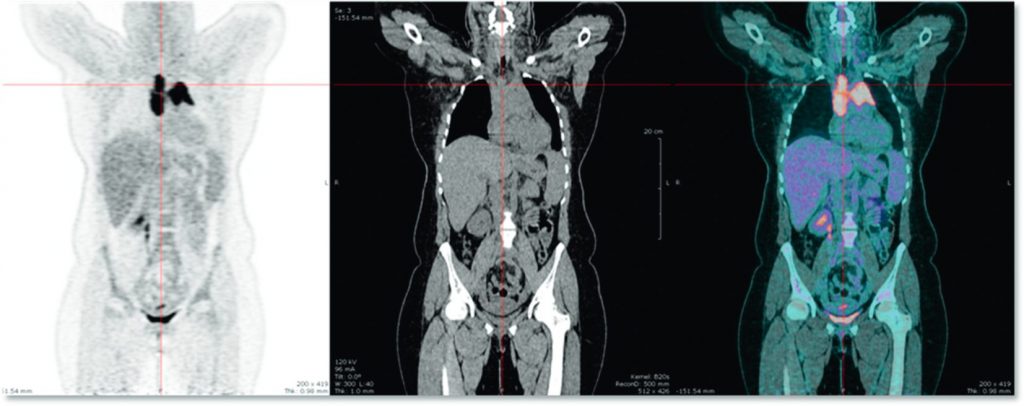

La majorité des lymphomes est avide du 18F-fluorodésoxyglucose (18FDG), traceur utilisé en routine pour l’imagerie TEP (TEP-TDM au 18FDG), et cette avidité pour le 18FDG est > 90 % dans le LH, le LBDGC et le LF, types histologiques qui représentent 70 % de l’ensemble des lymphomes. La TEP-TDM au 18FDG (figure 94.3) est recommandée au bilan initial des LF, LH et LBDGC et autres lymphomes avides de 18FDG. Elle permet d’une part d’améliorer la qualité de la stadification de l’atteinte lymphatique ou extralymphatique en complétant les données de la TDM et, d’autre part, de faciliter l’évaluation de la réponse thérapeutique (figure 94.4). De plus, la TEP-TDM au 18FDG est recommandée pour le bilan d’extension ostéomédullaire des LH et des LBDGC et permet de surseoir, dans la grande majorité des cas, à la réalisation systématique de la biopsie ostéomédullaire. Depuis 2014, l’étendue de la maladie est appréciée en TEP-TDM au 18FDG selon la classification de Lugano.

Fig. 94.3. TEP-TDM au 18FDG : lymphome de Hodgkin

Images coronales montrant une volumineuse masse médiastinale avide de FDG.

Source : CERF, CNEBMN, 2022.